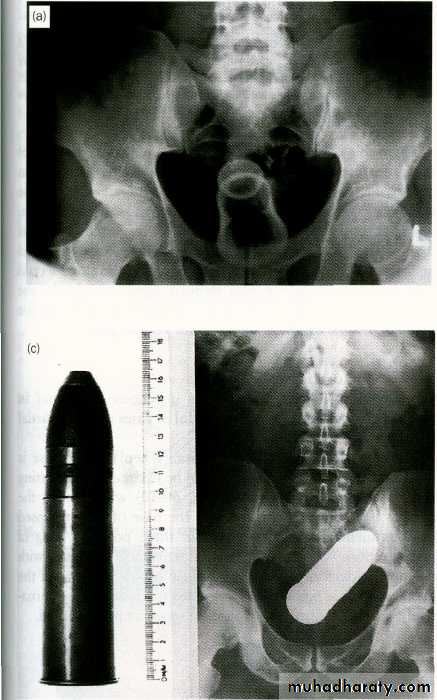

7-Insertion of a foreign body

Foreign bodies in the rectum

Treatment

- good clinical examination.- investigation such as proctoscope, sigmoidoscope if possible ,ultra-sound and ct-scan